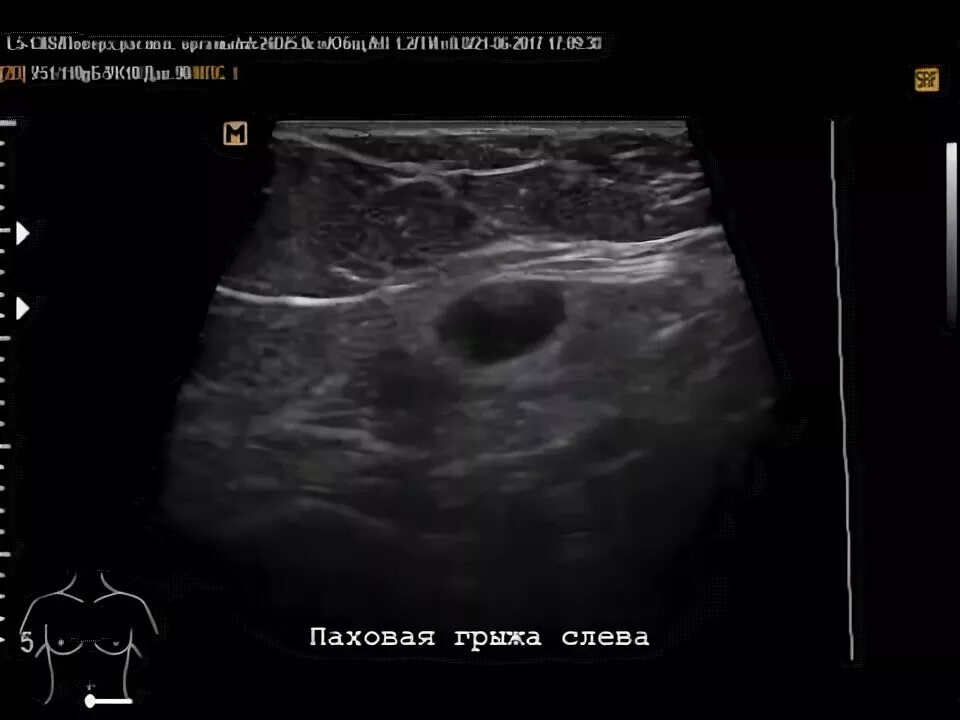

Грыжа узи заключение